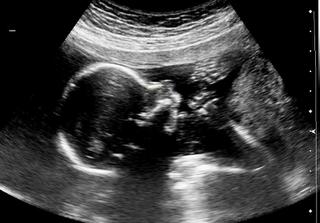

dnes som bola aj s mangelíkom na morfo sone, všetko je OK, aj podľa tohto sona sme o týždeň väčší a už vieme, že budeme mať chlapčeka 🙂 🙂 🙂 moc sa z toho tešíme